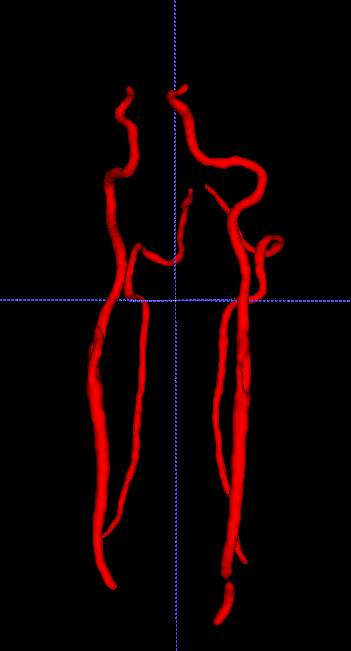

To address the drawbacks of existing approaches, we introduce a network structure which is able to generate accurate volumetric segmentation masks of very large 3D volumes. The main idea is to integrate maximum intensity projection (MIP) layers from different directions which transform the data to 2D images containing information of the full 3D image. As an example, we test the network for segmenting blood vessels (arteries and veins) in magnetic resonance angiography (MRA) scans (Figure 1.1).

We aim at generating volumetric binary segmentation masks. In particular, as one targeted application, we aim at segmenting blood vessels (arteries and veins) which assists the doctor to detect abnormalities like stenosis or aneurysms. Furthermore, the medical sector is looking for a fully automated method to evaluate large cohorts in the future. The Department of Neuroradiology Innsbruck has provided volumetric MRA scans of 119 different patients. The images face the arteries and veins between the brain and the chest. Fortunately, also the volumetric segmentation masks (ground truths) of these 119 patients have been provided. These segmentation masks have been generated by hand which is long hard work (Figure 1.1).

We first solve a 2D version of our problem. This can be done by applying maximum intensity projections to the 3D data and the corresponding 3D ground truths. Using a rotation angle of around the vertical axis we obtain 10 MIP images out of each patient, which results in a data set to 1190 pairs of 2D images and corresponding 2D segmentation masks. Data corresponding for one patient are shown in Figure 2.1.